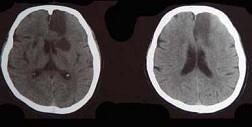

问题 头颅CT出现如图所示脑梗死,该病灶最可能是下列哪条阻塞引起()

选项 A.大脑前动脉主干 B.颈内动脉主干 C.大脑中动脉主干 D.脉络膜前动脉 E.豆纹动脉

答案 A